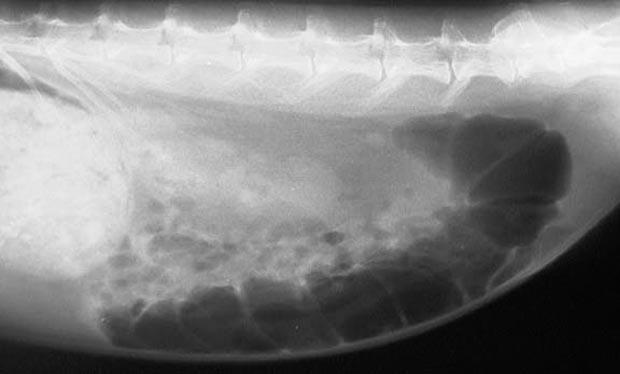

The cecum is the dark horizontal cylindrical object toward the bottom of this radiograph. The white circular area to the far left is the stomach. Photo courtesy of LBAH.